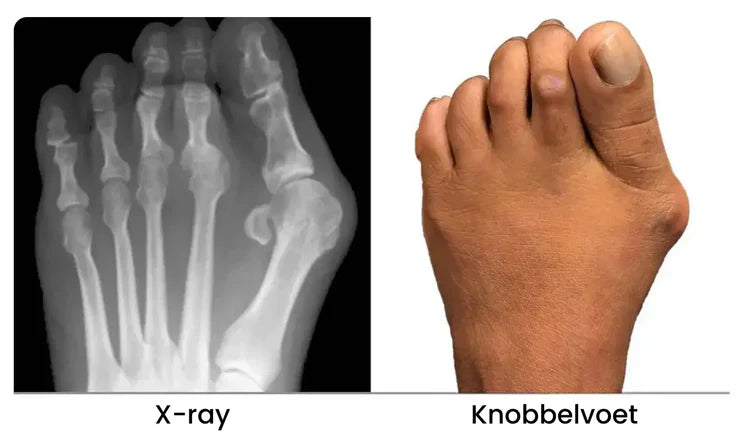

Die pijnlijke bult is niet zomaar "extra bot" dat chirurgisch verwijderd moet worden.

Wat er echt gebeurt is dat je grote teen ver uit zijn positie buigt.

De natuurlijke positie zou recht moeten zijn, net zoals de voeten van baby's eruitzien wanneer ze geboren worden.

De gevolgen? Het verstoort je dagelijks leven.

Zonder goede verzorging verergert de situatie—je tenen kunnen over elkaar heen gaan liggen, en problemen zoals hamertenen of botknobbels kunnen ontstaan.

Een scheefstaande teen herstelt niet vanzelf; deze verslechtert geleidelijk in de loop van de tijd.

Dit kan uiteindelijk leiden tot invasieve chirurgie, langdurige pijnmedicatie, of zelfs moeite met lopen.